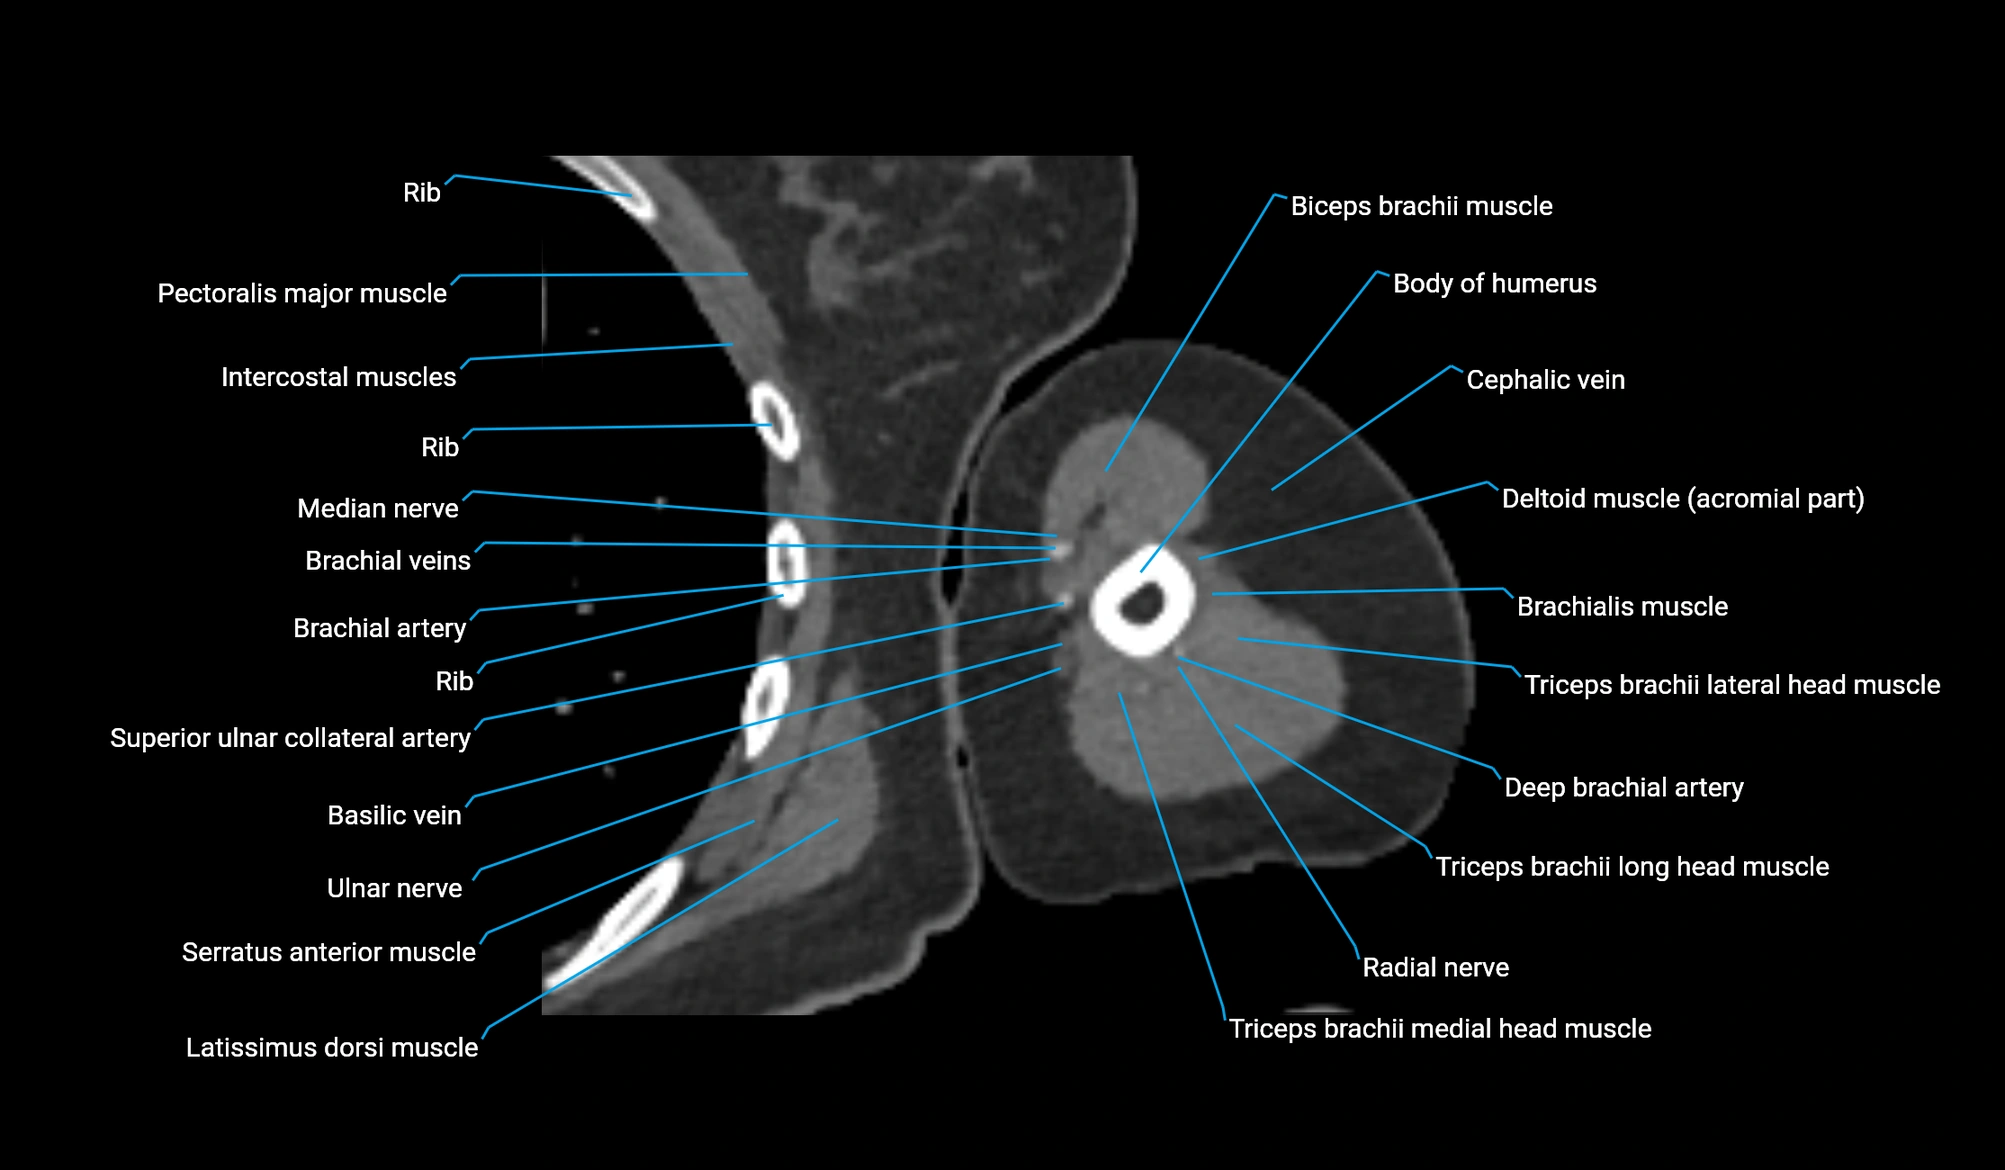

CT image